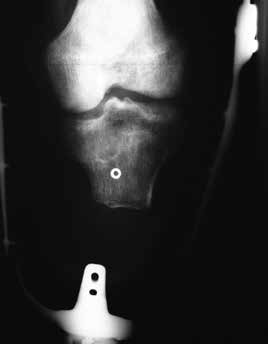

Mögliche Fehler bei der Unterschenkelamputation

Im Folgenden werden anhand von Fotos aus dem Archiv des Verfassers einige einschlägige Fälle vorgestellt, um häufig vorkommende Fehler aufzuzeigen (Abb. 1–10).